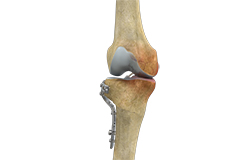

Knee Osteotomy

Knee osteotomy is a surgical procedure in which the upper shinbone (tibia) or lower thighbone (femur) is cut and realigned. It is usually performed in arthritic conditions affecting only one side of your knee.

High Tibial Osteotomy

High tibial osteotomy is a surgical procedure performed to relieve pressure on the damaged site of an arthritic knee joint. It is usually performed in arthritic conditions affecting only one side of your knee and the aim is to take pressure off the damaged area and shift it to the other side of your knee with healthy cartilage.